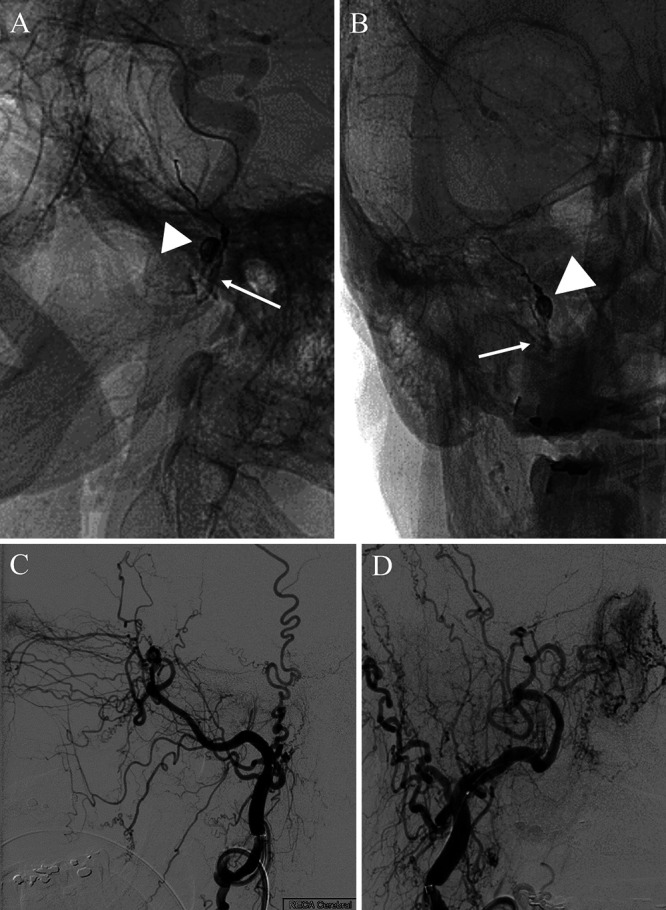

The patient was taken to the angiography suite for further characterization and definitive management. Catheterization of the MMA with microinjections opacifying the pseudoaneurysm and draining veins was performed (Fig. 2C–F). The distal intracranial MMA and its anastomosis to the ophthalmic artery were evaluated. This was followed by coil placement distal to the pseudoaneurysm (within the proximal skull base MMA and foramen spinosum) and subsequently Onyx-34 penetration casting the fistula and immediately proximal MMA supply until the internal maxillary artery was reached (Fig. 3A and B). Final images showed no residual arteriovenous fistula or pseudoaneurysm filling (Fig. 3C and D).

FIG. 3.

A and B: Lateral and frontal projections 4 months after placement of coils in the pseudoaneurysm (arrowheads) and Onyx-34 casting of the proximal MMA until the internal maxillary artery was reached (arrows). C and D: Lateral and frontal injections of the external carotid artery with interval resolution of pseudoaneurysm filling or fistulous connection.